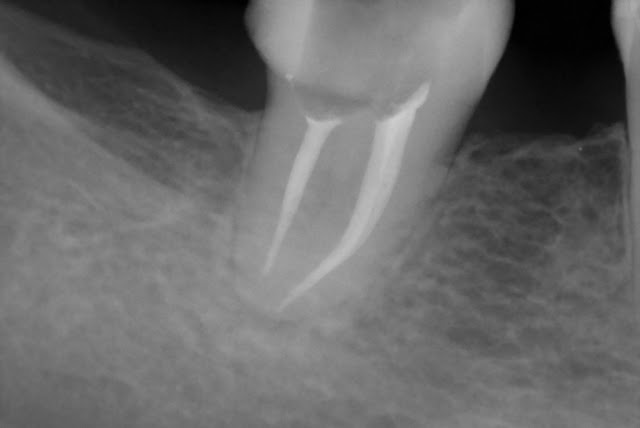

Czasami zastanawiamy się , czy jakiś ząb był leczony kanałowo. Najprościej sprawdzić to , robiąc zdjęcie rentgenowskie. Jeżeli widać na nim białe wypełnienie w korzeniu , taką niteczkę , to już jesteśmy pewni , że takie leczenie było przeprowadzone. Jeżeli ta niteczka , przebiega przez cały korzeń , to mamy potwierdzenie poprawnego wypełnienia kanału. Dodaję parę zdjęć rentgenowskich leczonych przeze mnie pacjentów.